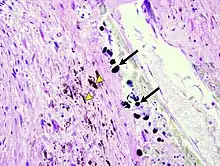

Micrograph of the spleen showing darkly stained, spheroid Gamna-Gandy bodies (arrows) outside the vessel wall at the center. Also shown is diffusely scattered, brown, granular hemosiderin pigment (arrowheads), indicating previous hemorrhage (hematoxylin & eosin staining, 40x magnification).

Gandy–Gamna nodules or Gandy-Gamna bodies, sometimes known as Gamna-Gandy bodies or Gamna-Gandy nodules, are small yellow-brown, brown, or rust-colored foci found in the spleen in patients with splenomegaly due to portal hypertension,[1] as well as sickle cell disease. They consist of fibrous tissue with haemosiderin and calcium deposits, and probably form due to scarring at sites of small perivascular haemorrhages.[2] They are visible on MRI scanning due to the presence of haemosiderin.[3]